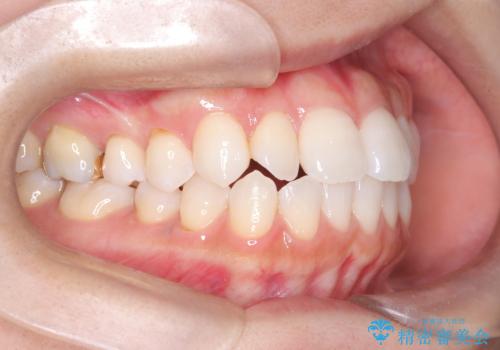

- 歯の捻じれやデコボコを主訴にご来院された患者様です。

矯正治療の精密検査を行った結果、非抜歯(歯を抜かない)矯正治療を選択いたしました。